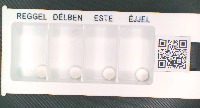

ogyei_v2_20 Computer Vision Project

downloadClasses (20)

akineton_2_mg

algoflex_rapid_400_mg

algopyrin_500_mg

cataflam_50_mg

controloc_20_mg

covercard_plus_10_mg_2_5_mg_5_mg

donalgin_250_mg

milgamma

naprosyn_250_mg

no_spa_40_mg

nootropil_1200_mg

normodipine_5_mg

olicard_60_mg

quamatel_40_mg

salazopyrin_en_500_mg

semicillin_500_mg

sicor_10_mg

syncumar_mite_1_mg

urzinol

voltaren_dolo_rapid_25_mg